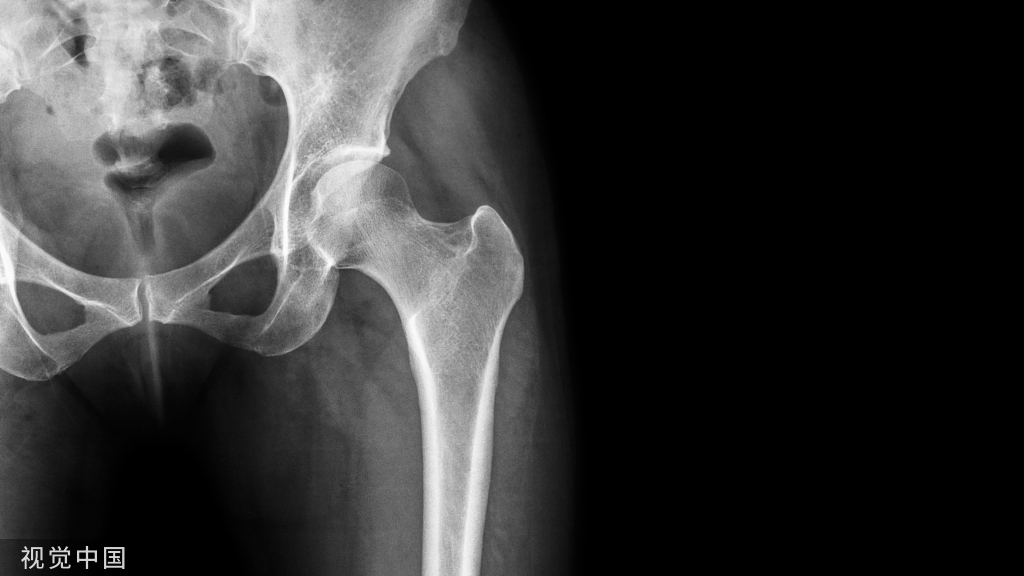

以股骨干骨折(AO分型)的几种典型代表,简单横形骨折(A3)、楔形骨折(B3)、多段骨折(C2)、严重粉碎骨折(C3)为例,如果选用LCP,如何打钉?工作距离如何把握?

简单骨折

对于横形骨折(A3),按照AO基本理念,骨折端应加压、追求绝对稳定和一期愈合。所以,首先应在骨折端两旁旁开2-3孔各打一枚普通皮质骨螺钉,利用偏心孔进行骨折端加压;然后在钢板两端置锁定钉(根据情况,可单皮质置钉,避免应力集中);再在加压螺钉与末端螺钉间随便各加1-2枚锁定钉;最后在普通钉靠近骨折线的锁定孔各打一枚锁定钉(普通钉的保护螺钉)。

螺钉不易过多,注意遵循长钢板(按AO原则,简单骨折钢板长度是骨折区长度的8-10倍,粉碎骨折钢板长度是骨折区长度的2-3倍)、少螺钉的应力分散原则(如下图示)。